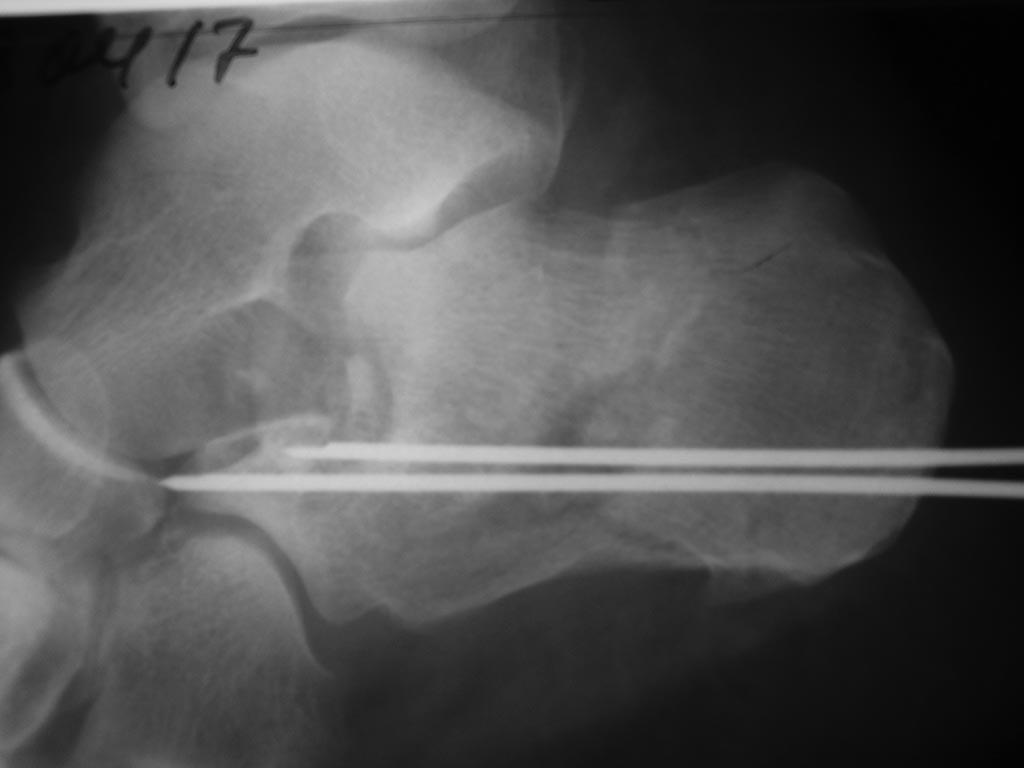

Перелом сложный, рентгенограмма после репозиции низкого качества и в одной проекции. На какой адекватный совет можно рассчитывать? Если же пытаться продумать операцию до мелочей, желательна КТ.

Насчет снимков согласен. Позже добавлю. КТ пока нет возможности сделать

Выкладываю еще снимки